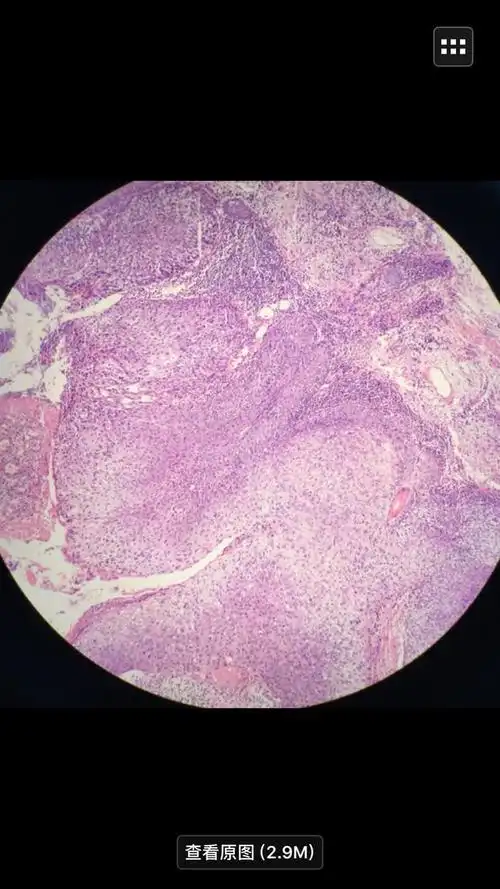

左面部皮肤原位癌一例